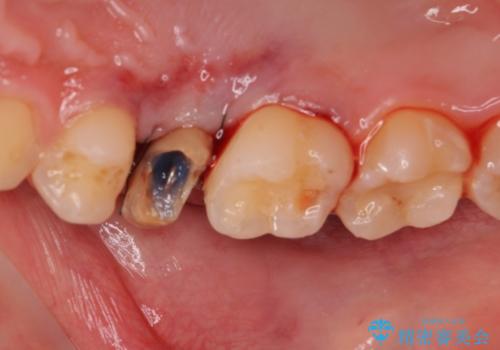

- 「左右どちらとも、どこかが痛む」とご来院された患者様です。

他院で虫歯治療を複数行っており、原因となりうる歯がいくつかありました。まずレントゲン上最もあやしい右上から治療開始しました。右上の歯は1本割れていたため、部分矯正で引っ張り出しました。

他院で虫歯治療を複数行っており、原因となりうる歯がいくつかありました。まずレントゲン上最もあやしい右上から治療開始しました。

右上の被せものを除去したところ、中で歯が割れていたため、部分矯正で引っ張り出すことになりました。